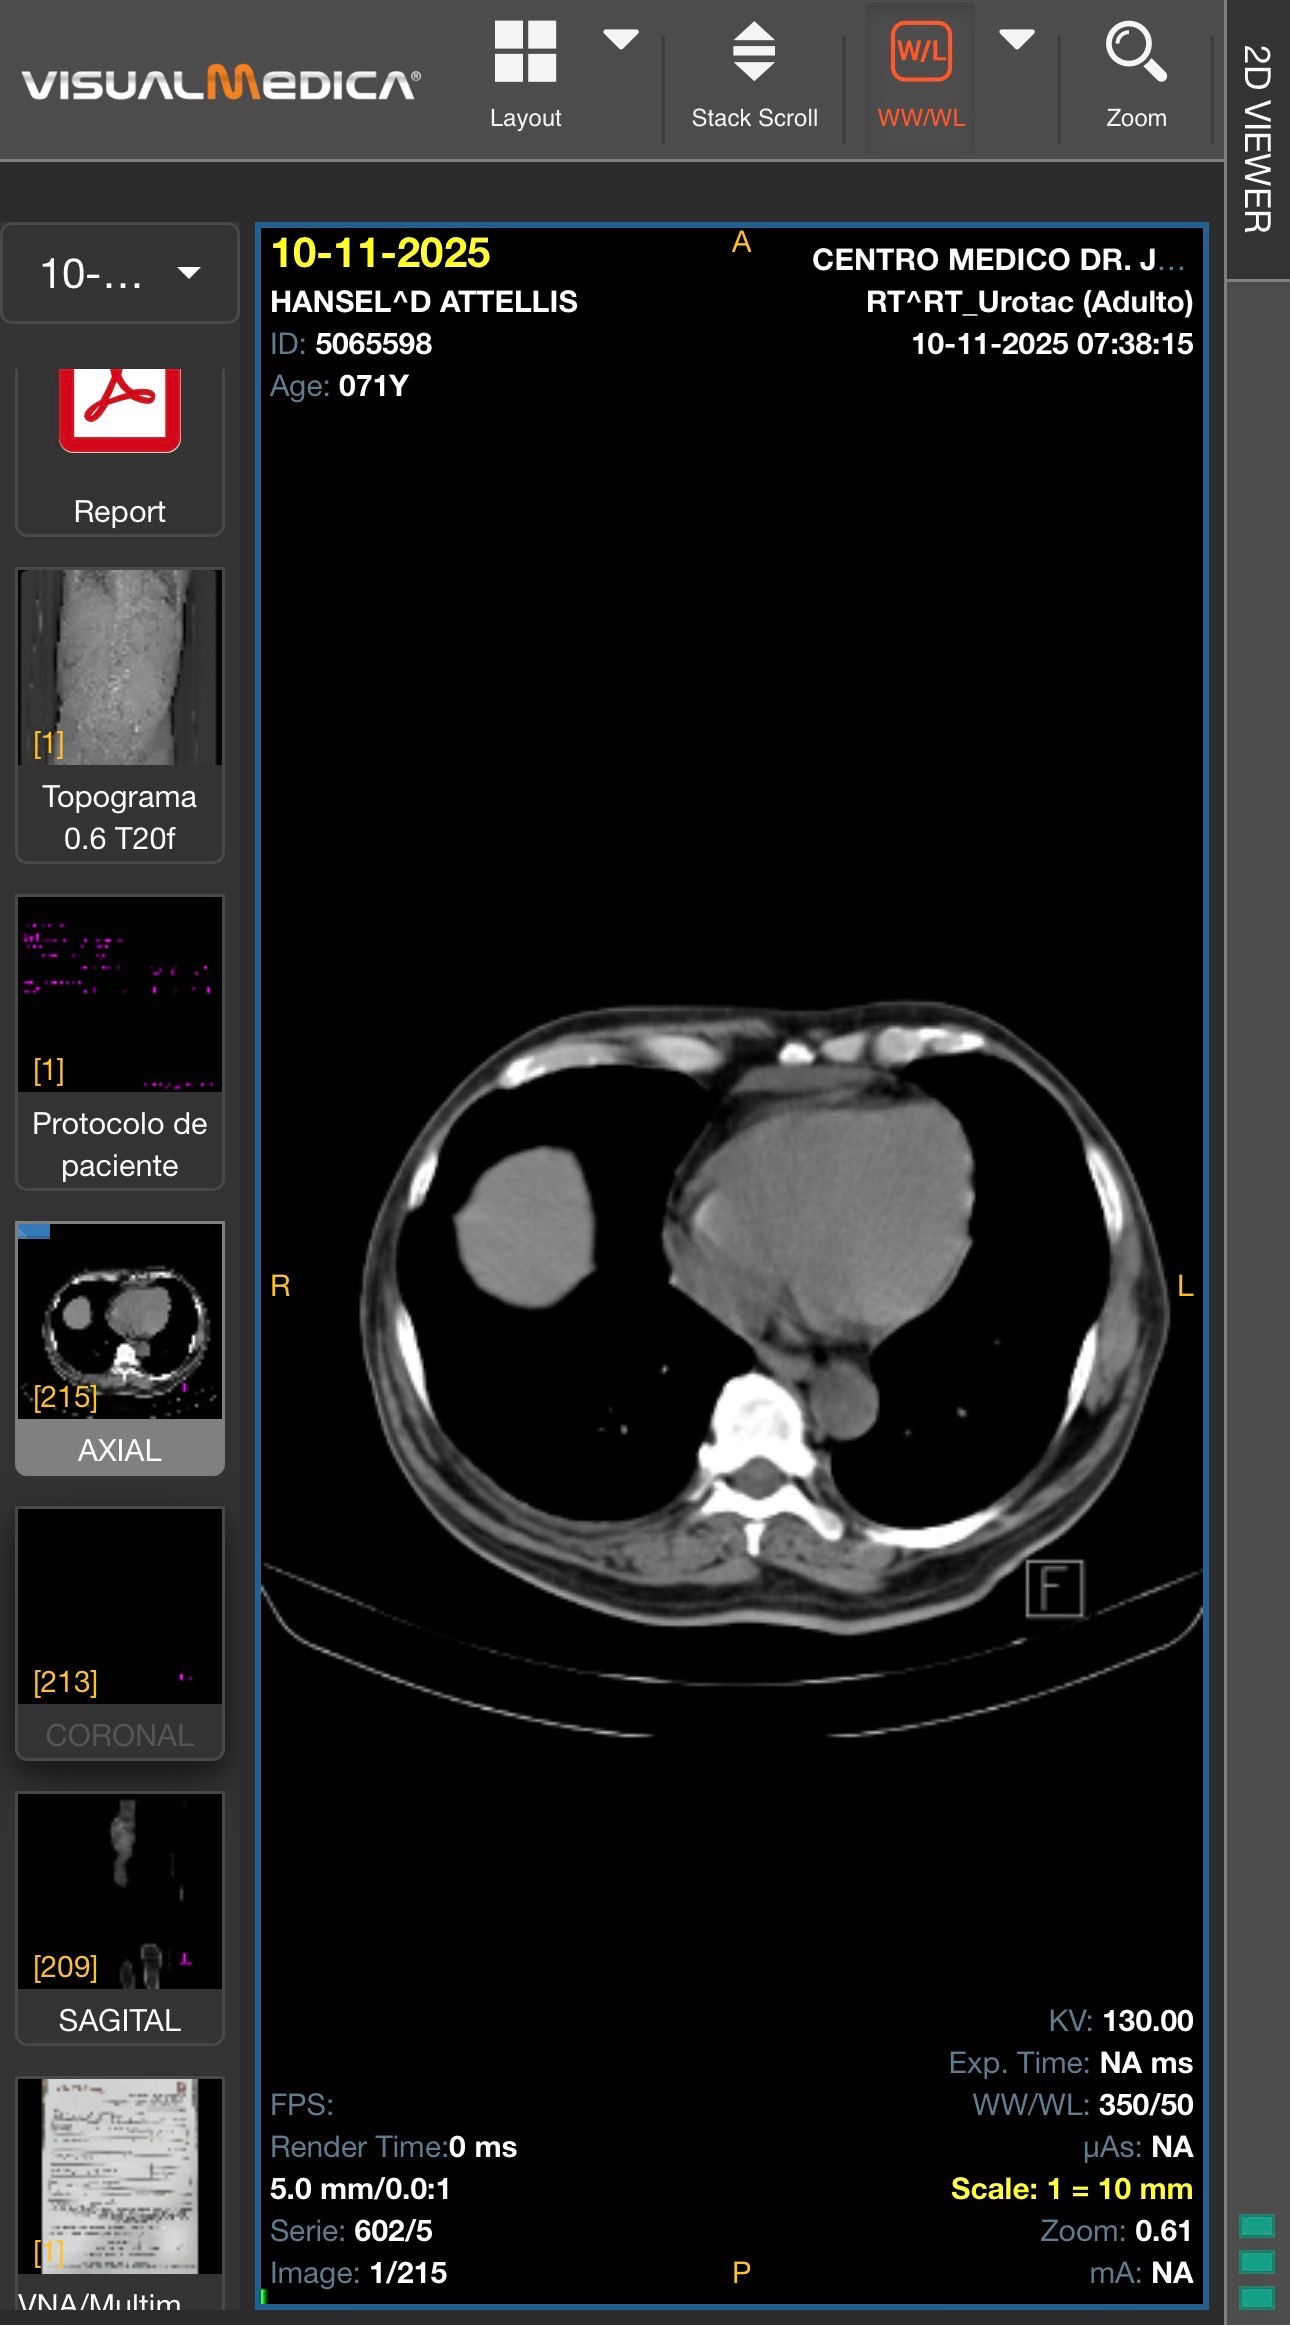

• Un quiste renal gigante en el riñón izquierdo (Bosniak II)

• Quistes múltiples en ambos riñones

• Riñón en herradura (malformación congénita)

• Hidronefrosis bilateral

• Atrofia del riñón derecho